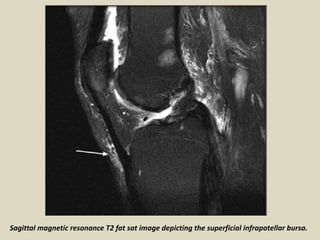

Sagittal magnetic resonance T2 fat sat image depicting the superficial infrapatellar bursa.

Superficial infrapatellar bursitis. A 42-year-old female presented with an anterior

knee swelling. Sagittal proton-density fat saturated (A) and sagittal gradient-echo

T2W (B) images show a distended superficial infrapatellar bursa (arrows)